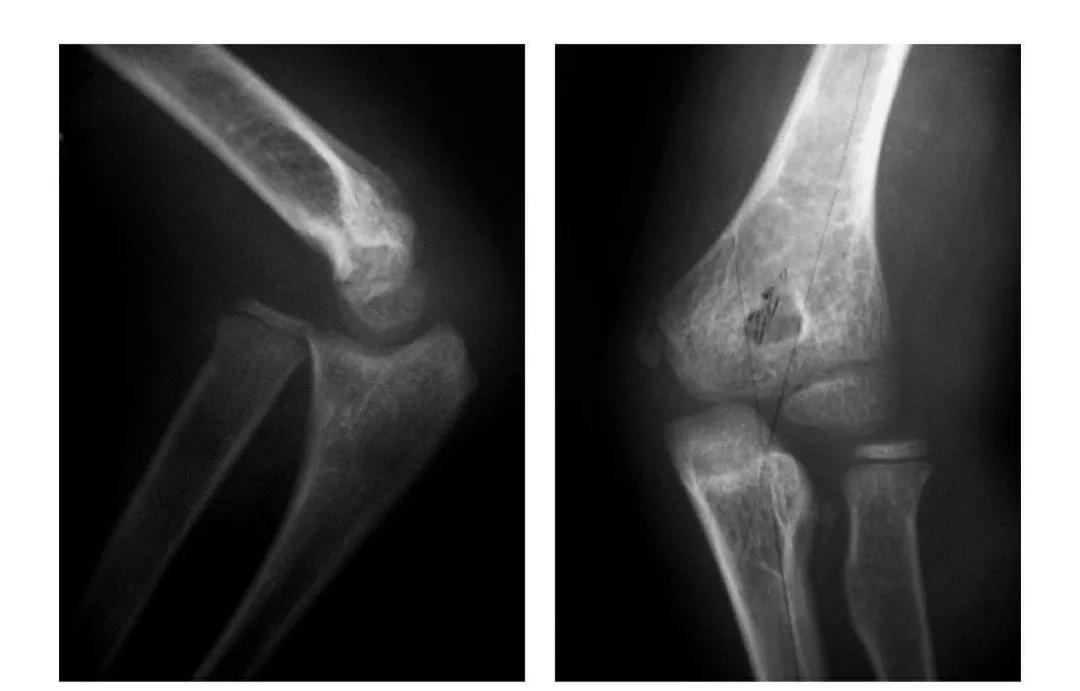

肘关节脱位与骨折脱位

肘关节后脱位

例1:肘关节过伸性半脱位。

例2:肘关节过伸性半脱位并肱骨小头外缘骨折。

例3:肘关节后侧脱位。

例4:肘关节后外侧脱位。

例5:肘关节后内侧脱位合并滑车后缘骨折。

例6:肘关节后外侧脱位合并外髁劈裂骨折。

例7:肘关节后外侧脱位并桡骨头劈裂骨折,致肱骨小头将桡骨头骨块推向肘关节内前侧。

例8:肘关节后侧脱位并桡骨头外侧关节面骨折与尺骨冠状突骨折,致该骨块移向肘关节内下方。